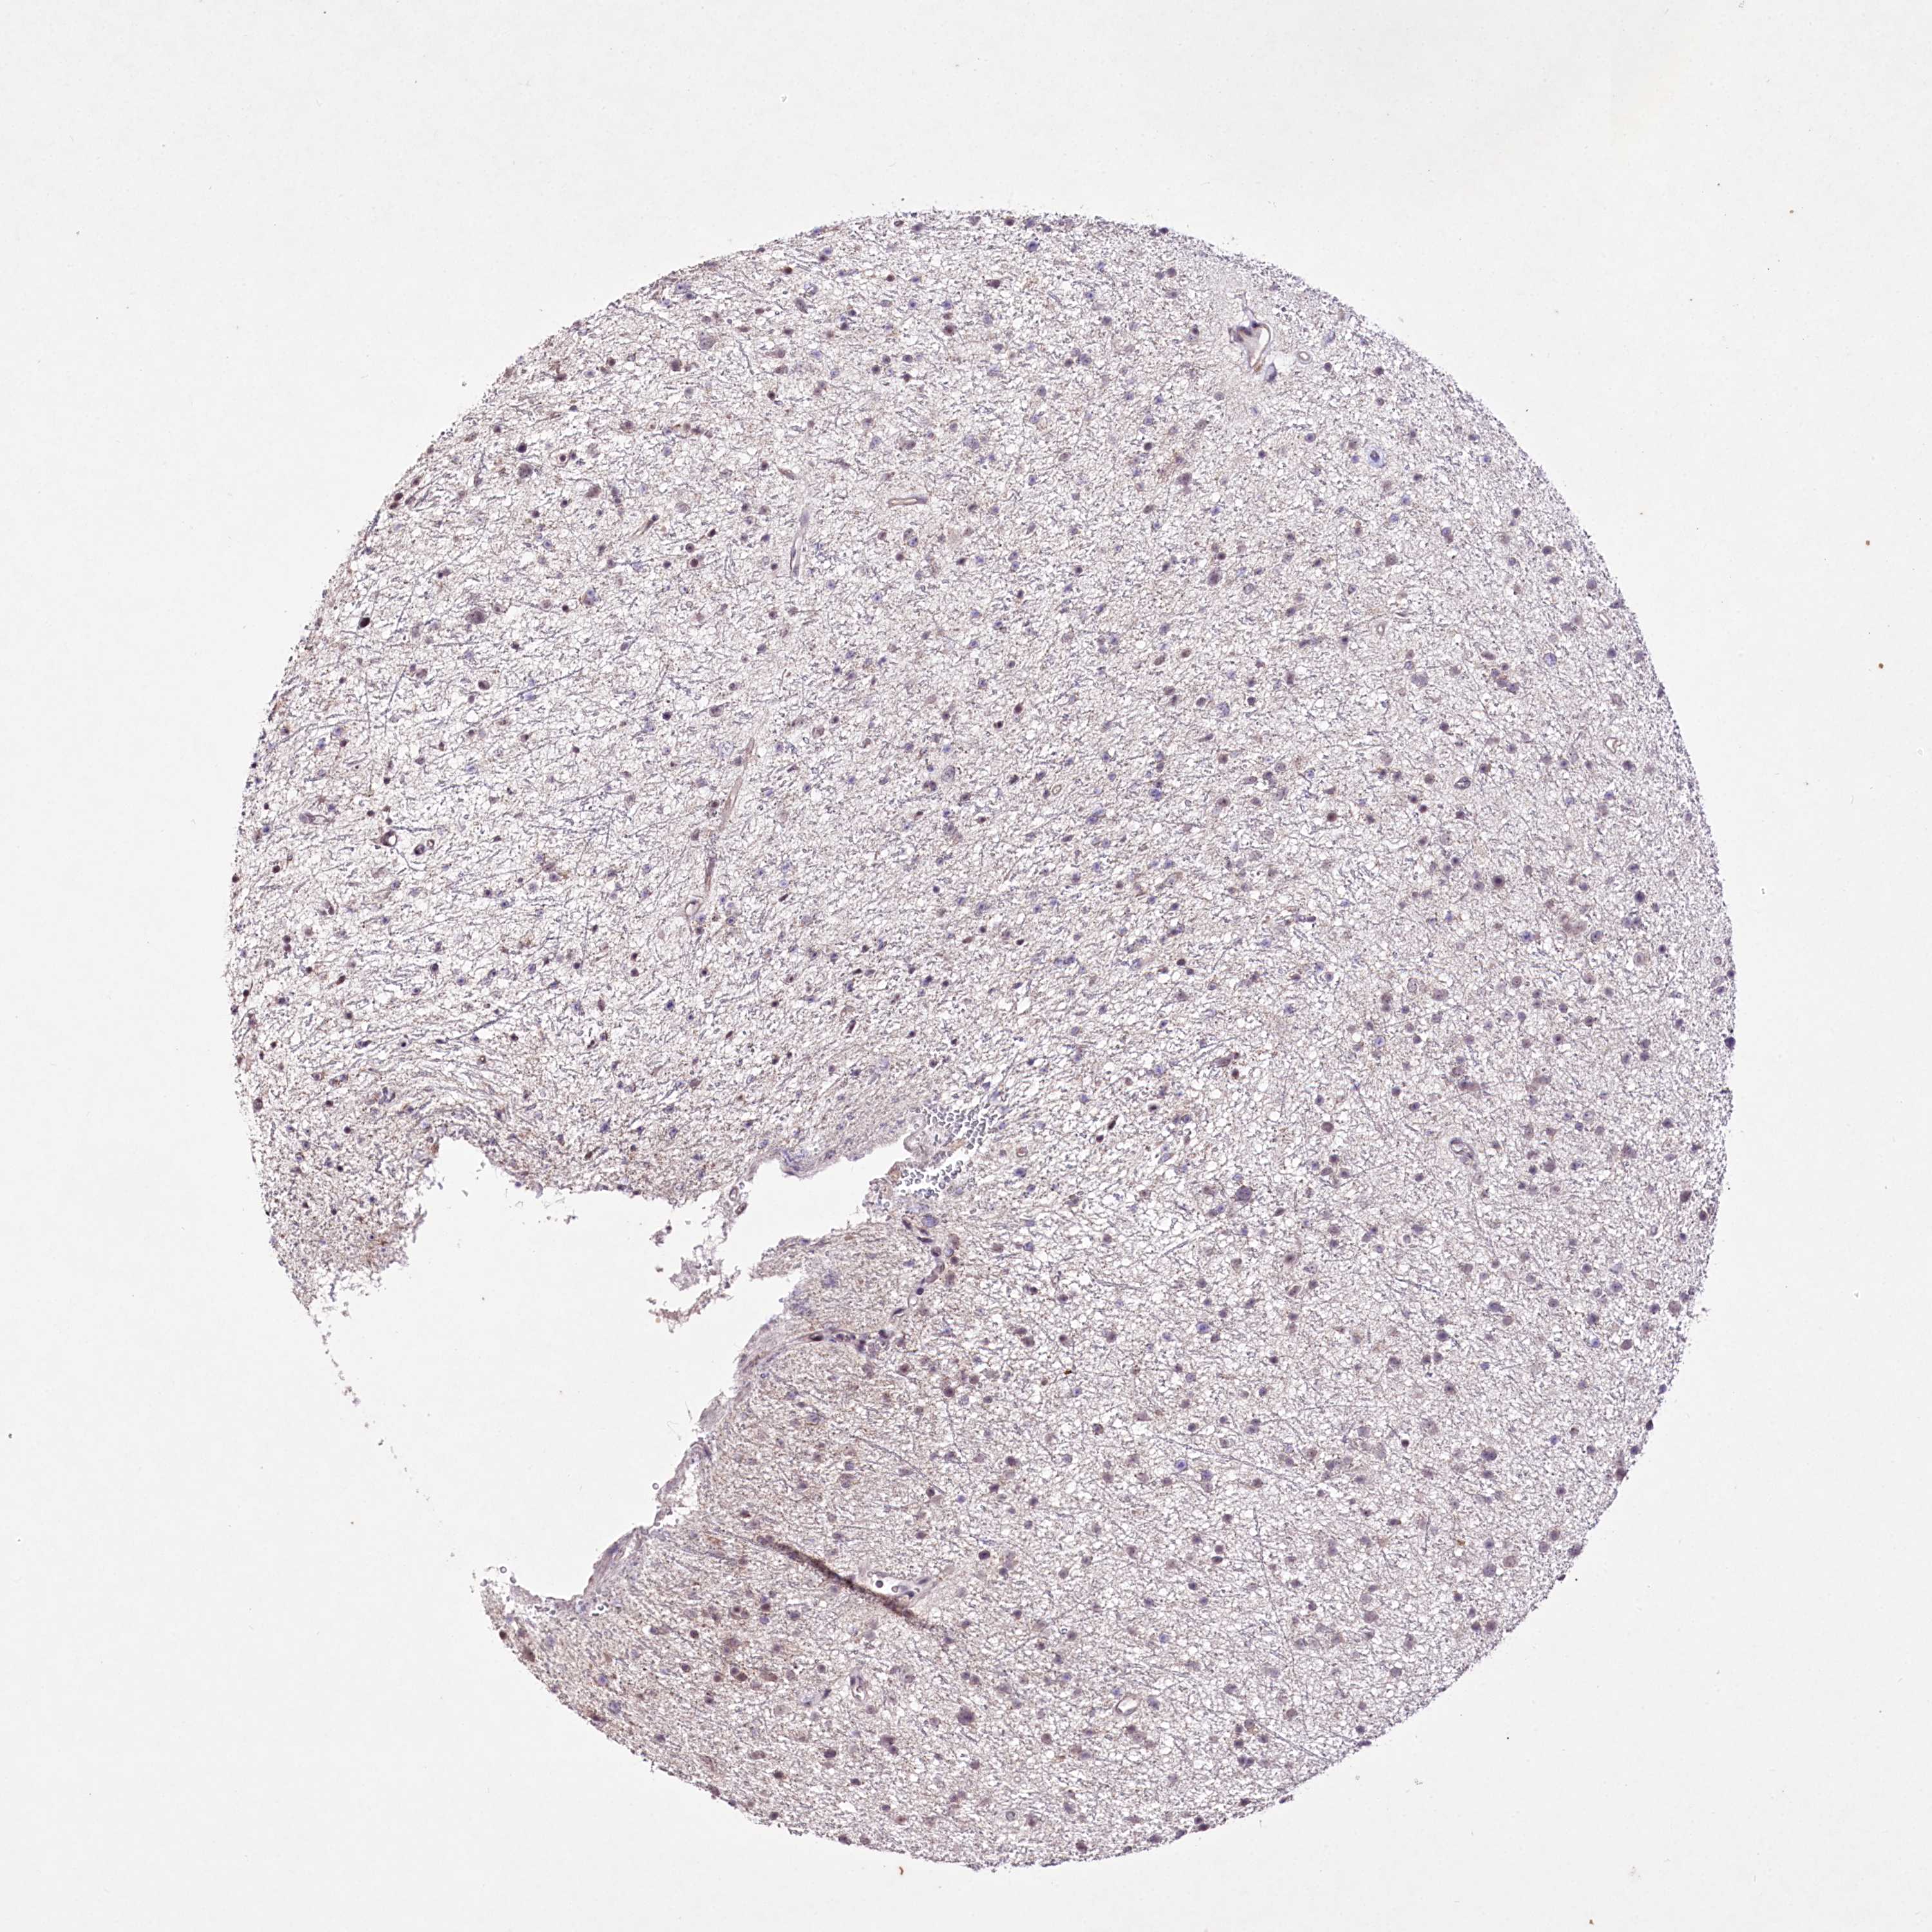

GLIOMA - Protein expressioni

A mouse-over function shows sample information and annotation data. Click on an image to view it in a full screen mode. Samples can be filtered based on level of antibody staining by selecting one or several of the following categories: high, medium, low and not detected. The assay and annotation is described here.

Note that samples used for immunohistochemistry by the Human Protein Atlas do not correspond to samples in the TCGA dataset.

Antibody stainingi

Antibody staining in the annotated cell types in the current human tissue is reported as not detected, low, medium, or high, based on conventional immunohistochemistry profiling in selected tissues. This score is based on the combination of the staining intensity and fraction of stained cells.

Each image is clickable and will lead to virtual microscopy that enables deeper exploration of all samples and also displays staining intensity scores, fraction scores and subcellular localization as well as patient and tissue information for each sample.

Antibody HPA062066

Antibody CAB032904

Staining

High

Medium

Low

Not detected

Intensity

Strong

Moderate

Weak

Negative

Quantity

>75%

75%-25%

<25%

None

Location

Nuclear

Cytoplasmic/membranous

Cytoplasmic/membranous,nuclear

Glioma, malignant, Low grade

Glioma, malignant, High grade

Glioblastoma, NOS